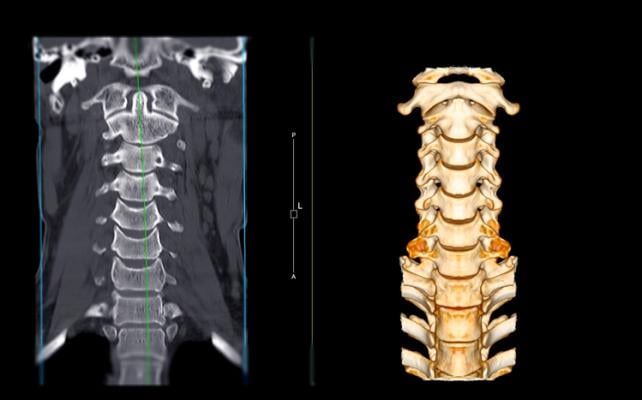

Imaging diagnosis of adult spine fractures is now almost exclusively performed with computed tomography (CT) instead of X-rays. Quickly detecting the location of any vertebral fractures is essential to prevent neurologic deterioration and paralysis after trauma. Researchers hope that AI can assist in expeditiously identifying and localizing fractures.

To create the ground truth dataset, the challenge planning task force collected imaging data sourced from 12 sites on six continents, including more than 1,400 CT exams with diagnosed cervical spine fractures, and an approximately equal number of negative exams. Spine radiology specialists from the ASNR and ASSR provided expert image level annotations these images to indicate the presence, vertebral level and location of any cervical spine fractures.

For the challenge competition, contestants will try to develop machine learning models that match the radiologists’ performance in detecting and localizing fractures within the seven vertebrae that comprise the cervical spine.